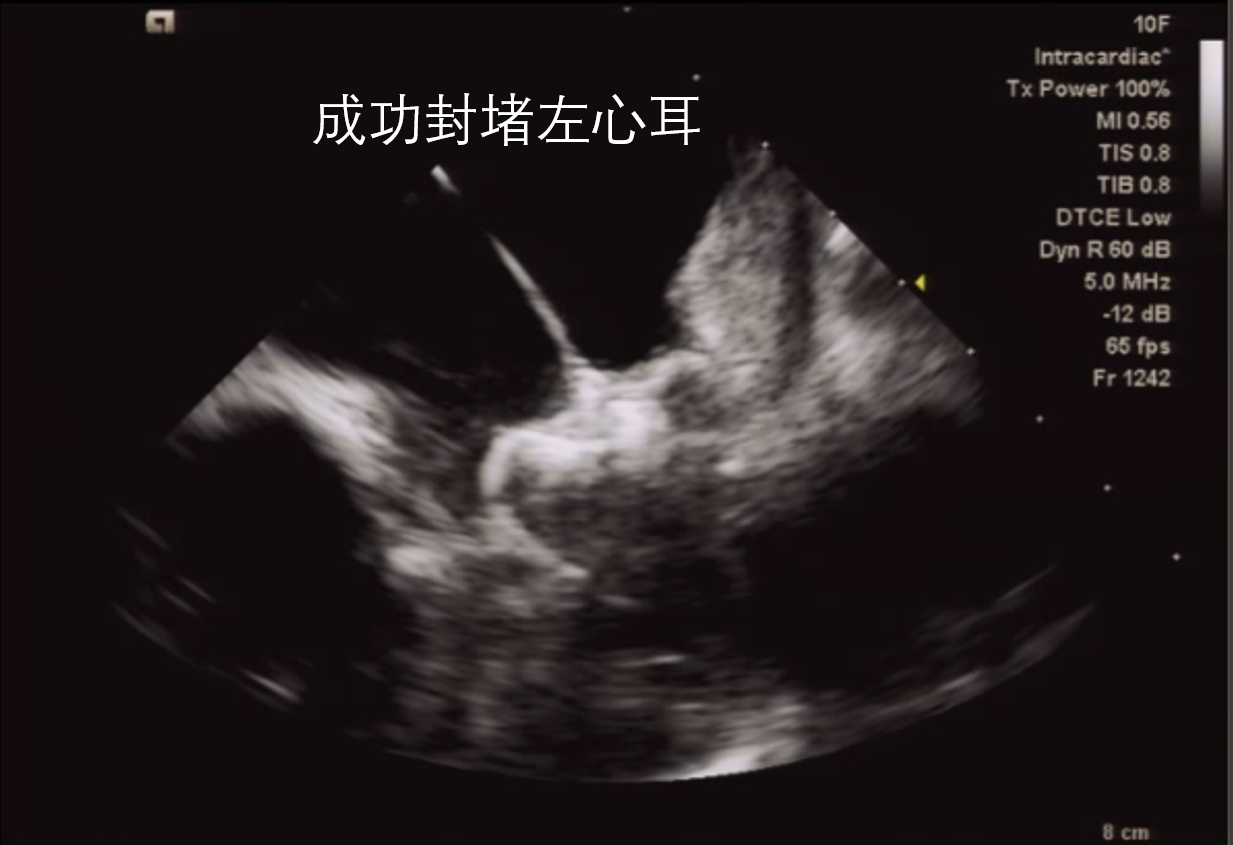

值得一提的是,此次手术在新的技术——心腔内超声(ICE)下施行。手术由周亚峰副院长指导、资深电生理专家陈弹主任以及董瑞庆博士主导的团队共同完成。患者全程清醒、无痛,安全返回病房。

心腔内超声(ICE)为一种有别传统超声的新技术,其可置入心腔内,可帮助术者更直观、精确地定位,减少手术并发症,提高手术成功率;同时,借助超声技术,减少射线的应用,实现绿色电生理,保障了患者及术者的安全。

(植入前准备)                          (植入后,封堵器呈草莓状,封堵完全,无残余分流)

此次手术为苏州市独墅湖医院(苏州大学附属独墅湖医院)首台ICE指导下左心耳封堵术,也是我市少有的基于ICE建模,局麻下完成的封堵术。其意义不仅在于为房颤患者提供新的预防卒中的策略,还标志着我院心内科团队在心脏介入诊疗领域迈上了新的台阶。未来,心内科团队将凭借过硬的实力及技术水平为园区及全市百姓提供更优质的医疗服务。